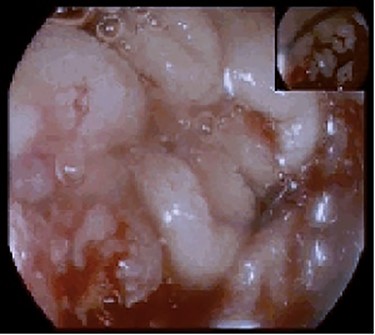

The patient was also being studied in our outpatient clinic for a symptomatic iron deficiency anaemia and had an upper gastrointestinal (GI) endoscopy performed the day before attending the ED. The endoscopy revealed a proliferative and ulcerated lesion involving the transition between the second and third portions of the duodenum (D2–D3; Fig. 1).

Upper endoscopy showing an ulcerative and friable duodenal lesion.